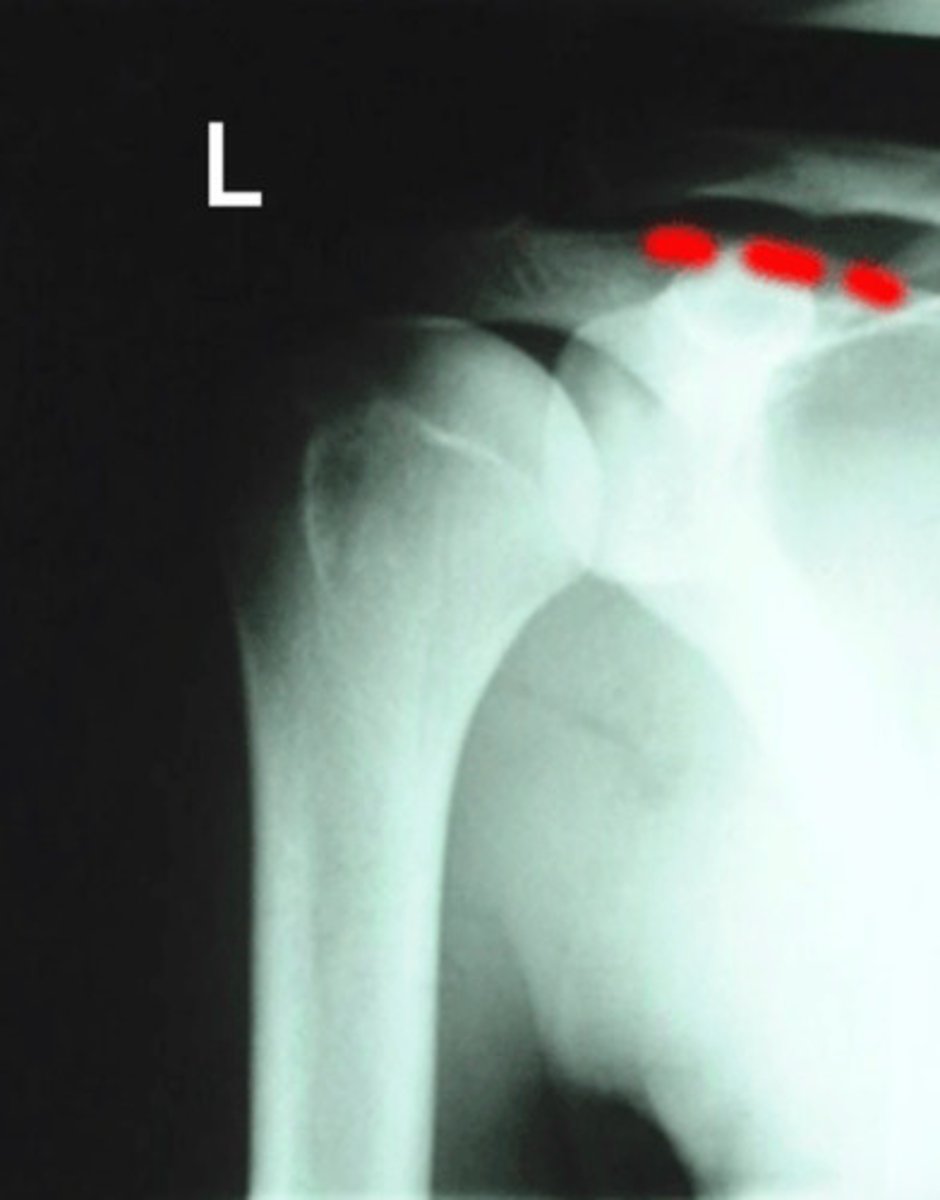

AC joint space

What space is being indicated in this image?

What is being indicated by the number 2?